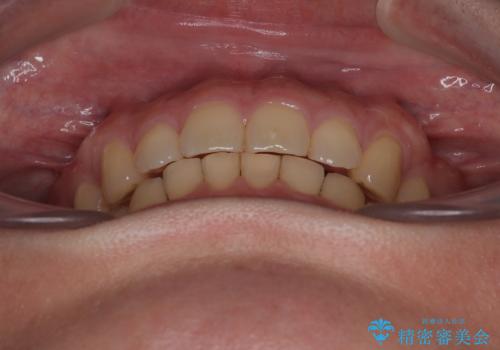

隠れた前歯が気になる ディープバイトのワイヤー矯正治療

下顎臼歯を起き上がらせるためにユーティリティーアーチを使用し、一気に深い咬み合わせを改善することができました。

- 1年7ヶ月